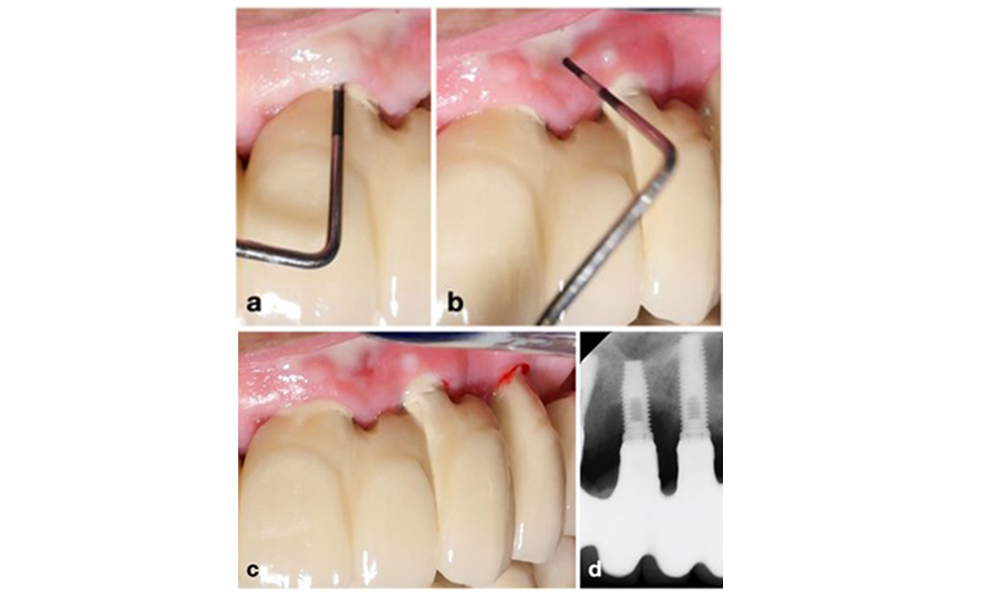

Le World Workshop on the Classification of Periodontal and Peri-Implant Diseases and Conditions de 2017 a établi des critères de diagnostic pour la mucosite péri-implantaire et la péri-implantite (Renvert et al. 2018). La mucosite péri-implantaire est définie comme (1) la présence d'une inflammation autour de l'implant (c'est-à-dire une rougeur, un gonflement, une ligne ou une goutte de saignement dans les 30 secondes suivant le sondage), associée à (2) l'absence de perte osseuse supplémentaire après la cicatrisation initiale (figure 1).

La péri-implantite est identifiée par (1) des signes d'inflammation similaires à la mucosite, (2) des preuves radiographiques de perte osseuse après la cicatrisation initiale et (3) une augmentation de la profondeur de sondage par rapport aux mesures prises peu après la mise en place de la reconstruction prothétique (figure 2). En l'absence de radiographies antérieures, un niveau osseux radiographique de ≥ 3 mm, accompagné d'un saignement au sondage et d'une profondeur de sondage ≥ 6 mm, indique une péri-implantite.

La perte osseuse attendue après la cicatrisation initiale, attribuée au remodelage de l'os marginal, varie en fonction de facteurs tels que le système ou le type d'implant. Par exemple, une perte osseuse de 1 à 2 mm est généralement considérée comme "normale" pour les implants au niveau de l'os avec une connexion externe (figure 2d, implant en position 23).